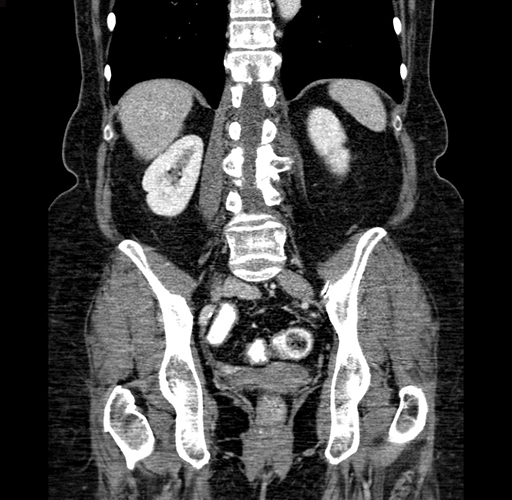

Pre-Chemo: Coronal Venous

Coronal Venous